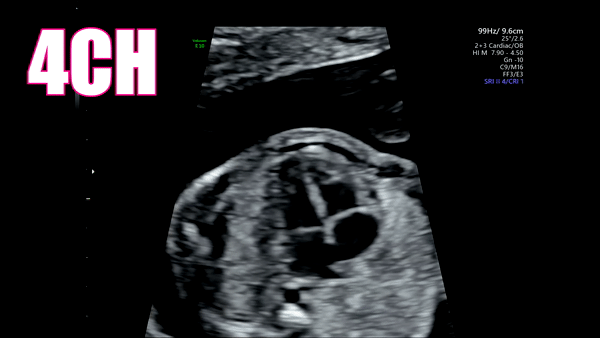

2nd: 4CH

This should be obtained in an apical or subcostal view. I take a few minutes here and just watch the heart. While I’m watching I’m asking myself: Are there 4 chambers? Are the ventricles the same size? Are the atrium the same size? Do I see the Aorta behind the left atrium? Do I see a moderator band in the right ventricle? Are the tricuspid and mitral valves opening and closing in sync? Does the heart have a normal rhythm? Does it take up approximately ⅓ of the chest? Is it angled in the chest properly? Look at how much information you can get from this one view!